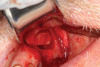

Dental implants are a predictable treatment option for the replacement of missing teeth. However, adjunctive surgical procedures may be required prior to implant placement. Sinus augmentation is indicated for cases in which deficient vertical bone height in the posterior region of the maxilla prevents dental implant placement. If inadequate residual bone height is present coronal to the maxillary sinus, the lateral sinus augmentation technique is recommended because it allows for the placement of larger volumes of graft material as well as greater access and visibility. In this technique, an osteotomy is made over the lateral sinus wall using rotary burs or a piezoelectric tip, taking care to keep the sinus mucosa intact (Figure 1). The sinus mucosa is then elevated (Figure 2), and a bone graft material is placed (Figure 3). Once healed, a significant increase in height and volume of bone can be seen radiographically (Figure 4 and Figure 5).

(2.) Elevation of Schneiderian membrane, demonstrating potential space prior to bone graft placement.

Figure 2

(3.) Placement of bone graft material into the lateral window.

Figure 3